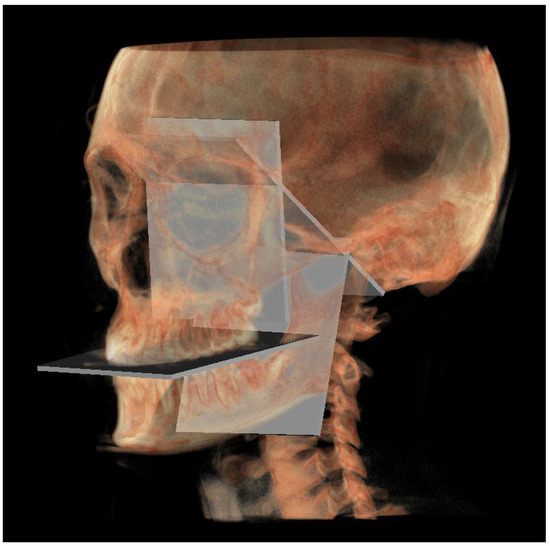

- The mandibular ramus plane (MR) (Figure 5) was identified by the following points: the middle points between the right and left condylion (mCo) and the right Gonion (rGo) and left Gonion (lGo). To adequately locate the mCo, it is advisable to draw a line on the frontal view from the right condylion to the left one to have a reference along which measure the mid-distance;

- The functional occlusal plane (FOP) (Figure 6) was identified by the posterior occlusal contact right side (rPoc), posterior occlusal contact left side (lPoc) and the middle point between the right and left anterior occlusal contact (mAoc). To adequately locate the mAoc, it is advisable to draw a line on the transversal view from the right mesial premolar contact to the left one to have a reference along which measure the distance.

| MR neutral (MRn) | Plane passing through the mCo, rGon and lGon |

| FOP neutral (FOPn) | Plane normal to the PMn passing through rPoc and lPoc |

| Construction plane through Co (CPCo) | Construction plane passing through the mCo and parallel to the PMn |

| GoP | Gonion plane: plane passing through rGo and lGo normal to PMn |